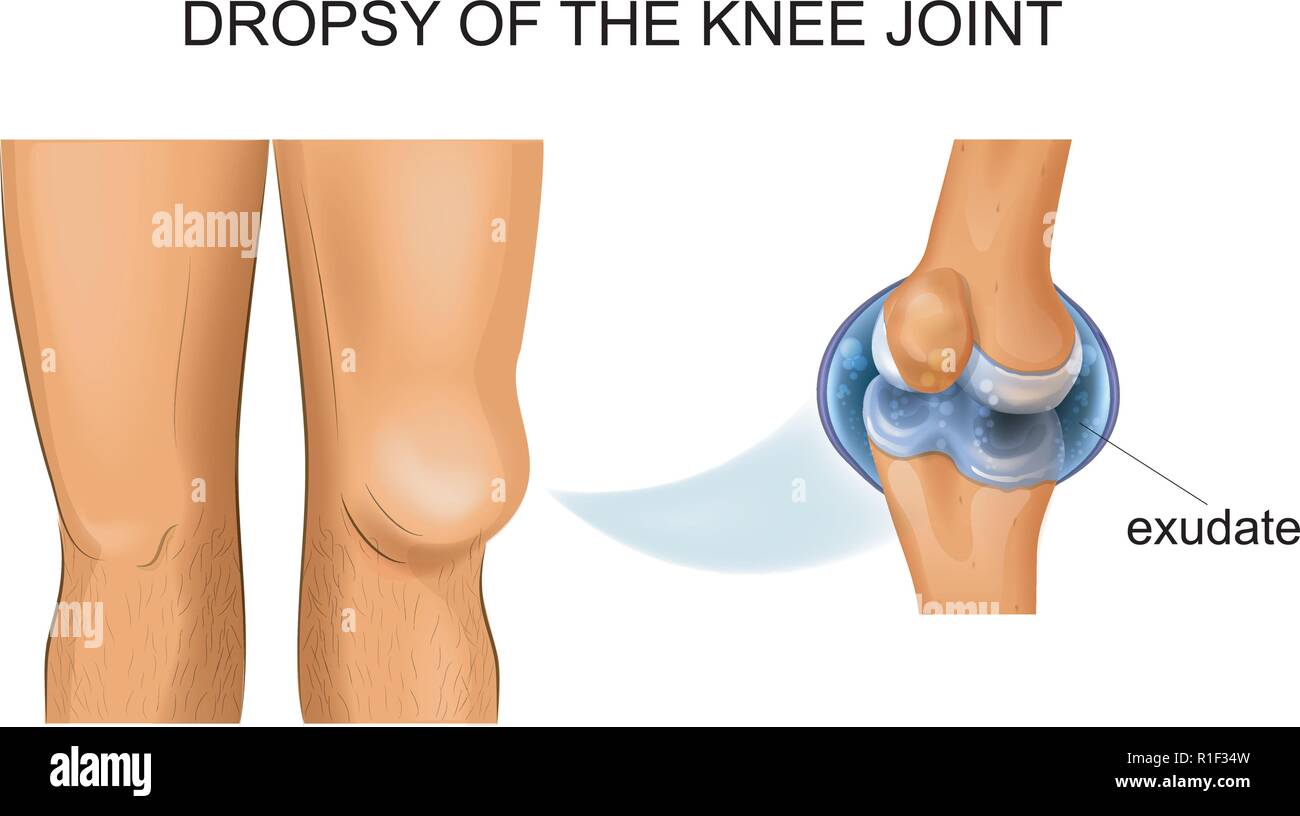

vector illustration of knee hydrarthrosis, articular dropsy Stock Vectorhttps://www.alamy.com/image-license-details/?v=1https://www.alamy.com/vector-illustration-of-knee-hydrarthrosis-articular-dropsy-image224681209.html

vector illustration of knee hydrarthrosis, articular dropsy Stock Vectorhttps://www.alamy.com/image-license-details/?v=1https://www.alamy.com/vector-illustration-of-knee-hydrarthrosis-articular-dropsy-image224681209.htmlRFR1F34W–vector illustration of knee hydrarthrosis, articular dropsy